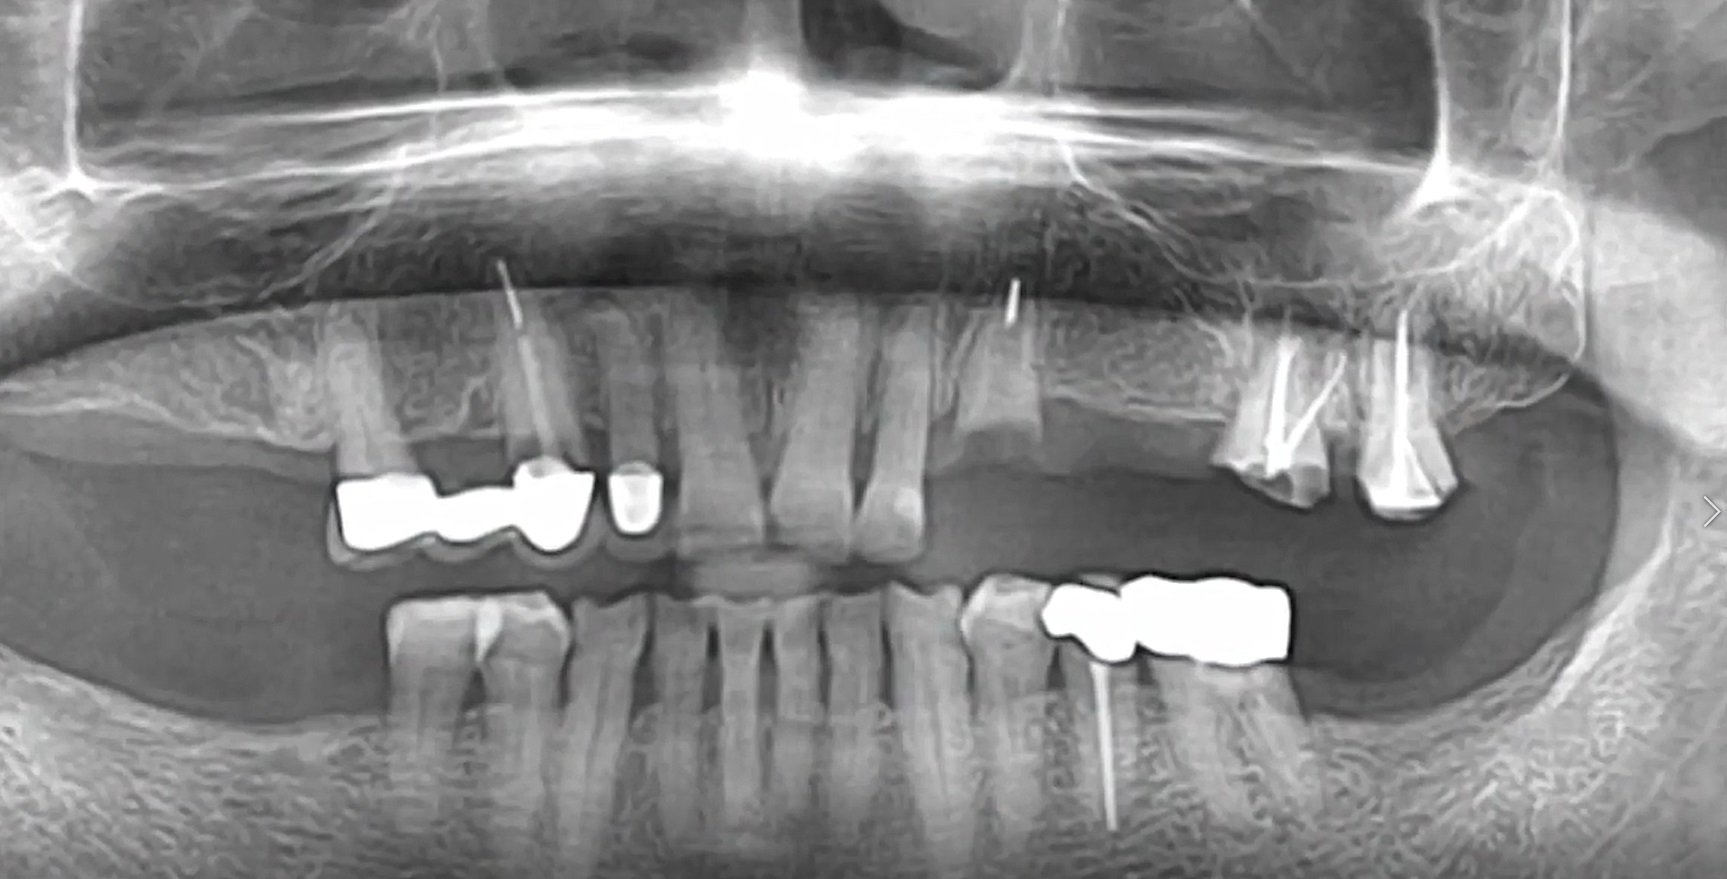

#11,#12,#23,#24 Root Membrane Technique with Digital R2GATE Surgery

Dr. Kwang Bum Park,Aesthetic zone,Digital Guided Surgery,Maxillary Anterior,Maxillary Posterior,#11,#12,#23,#24,Guided surgery,Root Membrane,AnyRidge,MiNi,R2GATE Guide,MEGA ISQ,Root Membrane Kit,R2GATE Surgical Kit(AnyRidge),Initial stability,Customized abutment,PMMA crown,Aesthetic…